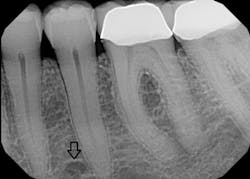

Figure 1: Abbreviated illustration of pathway: Incisive nerve (grays), mental nerve (black)

Figure 2: Mental foramen

Since only the soft tissues are anesthetized by the mental block, the incisive block is preferred for nonsurgical periodontal therapy procedures. The mental foramen, which opens anteriorly and superiorly, is usually located near the apex of the second premolar (see Figure 2), although studies indicate that it can be located from the distal of the canine to the first molar.3-5 It is advisable to check the radiographs and palpate the area prior to procedures to determine its location. The foramen appears as a round or oval radiolucency on radiographs (see Figures 3, 4) and may be palpable as a concavity or rough elevation.2

Figure 3: Panoramic radiograph of right and left mental foramina. (Courtesy of Bruce Dow, DDS)

Figure 4: Periapical radiograph of left mental foramen. (Courtesy of University of South Dakota Dental Hygiene Program)